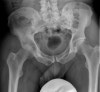

X-ray : 화농성 고관절염(Pyogenic arthritis, Septic arthritis)